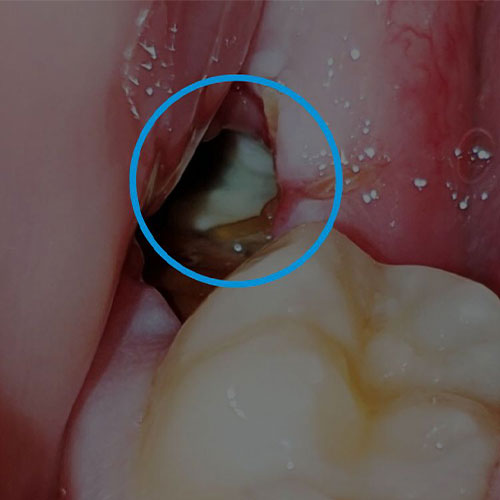

ترمیم دندان عقل معمولاً زمانی انجام می‌شود که این دندان دچار پوسیدگی شده باشد اما همچنان قابلیت درمان و حفظ شدن را داشته باشد. برخلاف تصور بسیاری، همه دندان‌های عقل نیاز به کشیدن ندارند؛ اگر دندان عقل کاملاً روییده، قابل دسترسی و سالم باشد، می‌توان آن را مانند سایر دندان‌ها ترمیم کرد. با این حال، تصمیم نهایی به موقعیت دندان، میزان پوسیدگی و نظر دندانپزشک بستگی دارد.

چه زمانی ترمیم دندان عقل امکان‌پذیر است؟

ترمیم دندان عقل در شرایط زیر انجام می‌شود:

• دندان عقل کاملاً از لثه بیرون آمده باشد.

• پوسیدگی سطحی یا متوسط داشته باشد.

• موقعیت دندان باعث گیر غذایی یا فشار روی دندان‌های دیگر نشود.

• دسترسی دندانپزشک به دندان برای درمان راحت باشد.